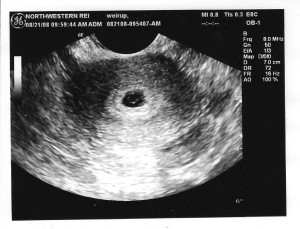

Ультразвук может показать беременность уже на 2–3 неделе акушерского срока, то есть после первой же недели задержки. Врач может установить беременность, исключить внематочную, определить количество плодов, вычислить копчико-теменной размер эмбриона, установить расположение хориона – будущая плаценты, с 4 недель он может уже увидеть сердцебиение. Правда, на этом сроке УЗИ делают только по показаниям: боли, кровотечение и т.д. Иногда, до 6-й недели плодного яйца на УЗИ не видно, тогда на помощь приходит анализ на ХГЧ.